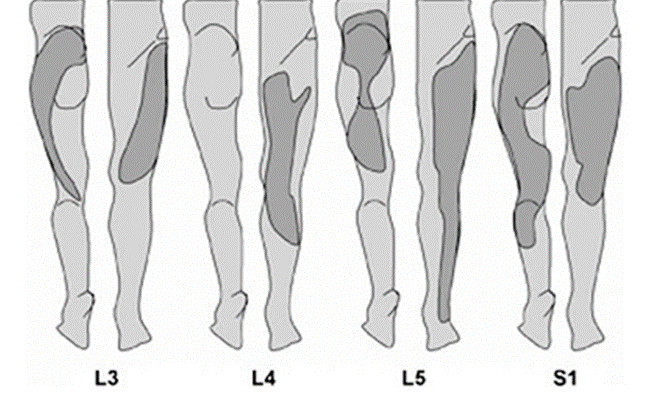

위에서 언급한 바와 같이, 요추 추간판탈출증의 탈출 부위에 따라서도 증상이 조금씩 다릅니다.

1) 요추 4 ~ 5번(L4-5)

- 압박되는 신경: 요추 5번(L5)

- 엉덩이에서 다리 뒤쪽으로 감각이 무뎌지며, 저리거나 당기는 통증이 발등과 엄지발까락까지 발생

2) 요추 5번 ~ 천추 1번(L5-S1)

- 압박되는 신경: 천추 1번(S1)

- 엉덩이 부위에서 다리 뒤쪽 중앙과 종아리 쪽으로 감각기 무뎌지며, 저리거나 당기는 통증이 발바닥과 새끼발가락까지 발생